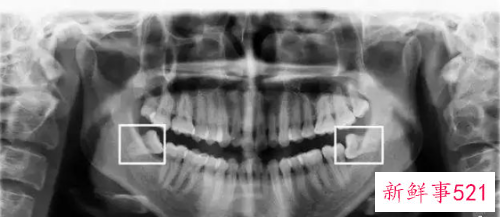

通常患者不自知,而由牙医以X光诊断得知。通常智齿萌发的空间不足,而会倒在第二大臼齿上,因而造成第二大臼齿清洁不易,甚至是牙齿部分吸收的现象,造成患者不舒适或牙疼。

3、智齿生长发育的空间不够会导致牙列不齐,有时会往第二磨牙牙根上靠拢侵犯邻牙,导致第二磨牙龋坏或者牙根吸收的情况。

智齿生长方向顶着前牙牙颈部或牙根,顶在牙颈部时第七颗牙会发生龋坏,智齿也会发生龋坏,因为没有生长空间还会推动牙齿变得牙列拥挤。

5、拔智齿的时候医生会建议拍片,智齿的多变性比较大,拍片虽说是辅助却是必不可少的,小到牙片大到曲面断层甚至是CT。

如果说我们拔一颗智齿我们所能看到的只有这颗牙表面这一层牙釉质,甚至有的时候我们根本看不到这颗智齿,它生长的方向,牙根弯曲程度,牙根数目,根尖是否有炎症等等,上颌我们更需要知道上颌窦与根尖的距离,下颌神经管与牙齿之间的距离,所以我们需要拍片来了解这颗牙的位置、难度,以及治疗方法。